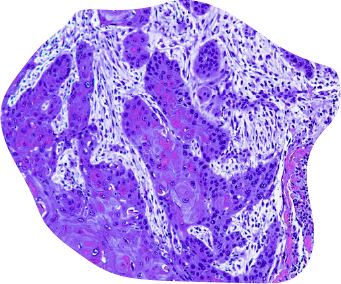

Mutations cellulaires

Lors des divisions, des erreurs peuvent survenir dans le code génétique des cellules. Le corps répare généralement ces anomalies, mais certaines peuvent échapper à ce contrôle. Quand les mutations s’accumulent, la cellule devient anormale : elle se comporte de manière désorganisée, se multiplie excessivement et peut former une tumeur.

Tumeurs bénignes &

tumeurs malignes

Toutes les tumeurs ne sont pas cancéreuses. Les tumeurs bénignes sont des amas de cellules non cancéreuses. Elles se développent lentement, restent localisées et ne présentent pas de risque de récidive si elles sont retirées complètement.

Les tumeurs malignes, elles, sont cancéreuses. Elles peuvent envahir les tissus voisins et se propager dans le corps.